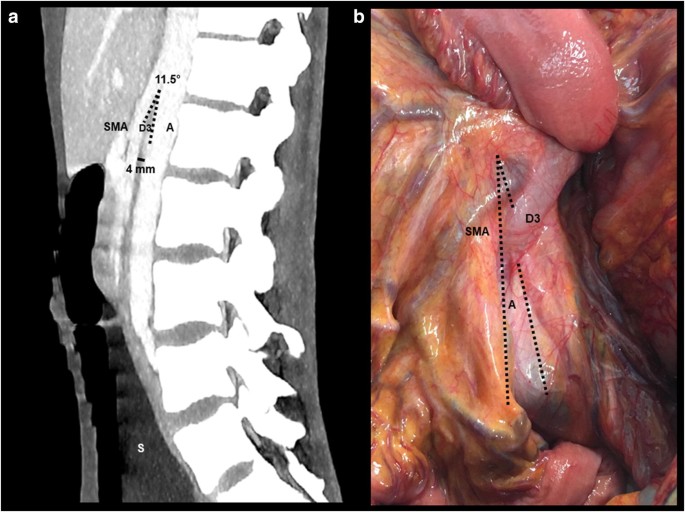

Superior mesenteric artery syndrome SMAS is an unusual condition where the third part of the duodenum is compressed between the superior mesenteric artery and the aorta. Symptoms and signs suggestive of this condition are nonspecific and a high index of suspicion coupled with appropriate imaging studies are necessary for diagnosis. If nutrition support is needed dietitians can tailor the nutrition prescription to the patients specific needs. Reversing or removing the precipitating factor is usually successful in a patient with acute superior mesenteric artery SMA syndrome. Feeding through a catheter parenteral nutrition Gastric decompression using a nasogastric tube Electrolyte correction Fluid resuscitation Posture therapy.

CONCLUSIONS Superior mesenteric artery syndrome is to be suspected in patients with abdominal pain following weight loss. There are no available data for outcomes in childrens idiopathic superior mesenteric artery syndrome SMAS strictly treated conservatively. SMAS superior mesenteric artery syndrome is a highly rare digestive condition that presents when the superior mesenteric artery causes an obstruction of the small intestine specifically the duodenum. Full recovery and resolution of symptoms often includes weight gain to restore the mesenteric fat pad and widen the angle between the aorta. This syndrome is a well-recognized entity in the current literature.